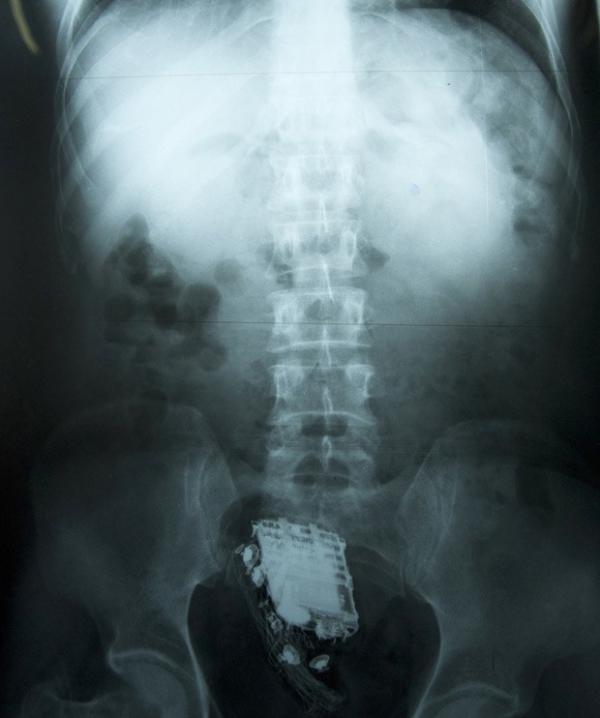

Raio-X mostra o telefone celular no reto de prisioneiro de 58 anos em Colombo, no Sri Lanka

Um prisioneiro do Sri Lanka que tentou esconder seu telefone celular durante uma inspeção em sua cela foi descoberto quando os guardas ouviram toques vindos de suas nádegas, informou um funcionário dos serviços médicos nesta sexta-feira (8).

O condenado de 58 anos de idade precisou ser internado no hospital nacional em Colombo, onde os médicos mais tarde retiraram o aparelho de seu reto.

O preso está cumprindo uma pena de 10 anos por roubo na prisão de segurança máxima de Welikada, na capital.

Ele disse que o homem permaneceu no hospital por dois dias, mas recebeu alta e foi enviado de volta para a prisão nesta sexta-feira, depois que o celular foi retirado.